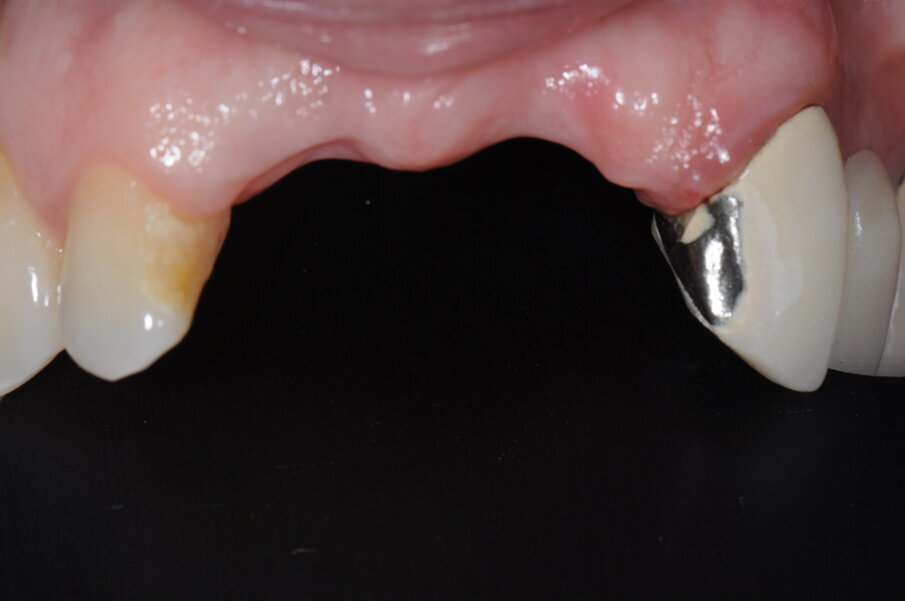

La paziente, donna, di anni 55, era giunta alla nostra osservazione richiedendo una riabilitazione protesica in area estetica a seguito di trauma provocato da un incidente stradale, avvenuto da circa 10 anni, che aveva determinando la perdita di due incisivi superiori in posizione 2.1, 2.2 (Figg. 1, 2).

Fig. 1 - Situazione iniziale della paziente al momento della prima visita.

Fig. 2 - Visione frontale della zona edentula.